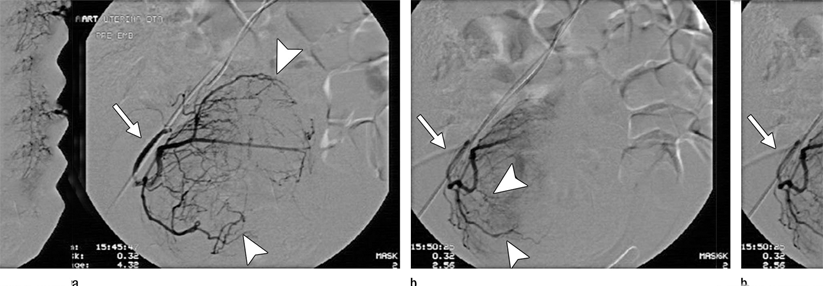

Myomembolisation:

• kann zur Verkleinerung der Myome, Besserung der Blutungsstörungen und Linderung von Symptomen führen

• Schädigung des Endometriums und Verminderung der ovariellen Reserve möglich

• nicht bei Kinderwunsch